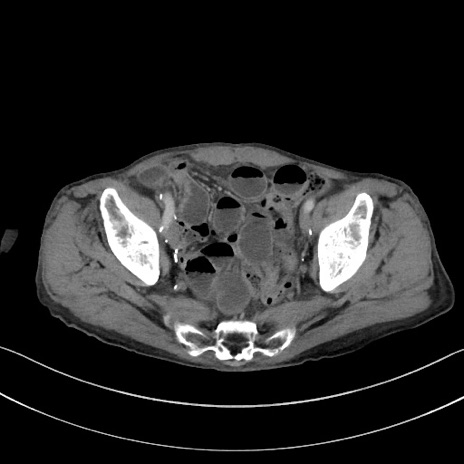

症例3(横断像)

【症例】 70歳代男性

【主訴】右鼠径部腫瘤、疼痛

【現病歴】本日朝より上記主訴あり、受診。

【既往歴】膀胱癌にて膀胱全摘、両側尿管皮膚瘻

【データ】WBC 5600、CRP 0.56